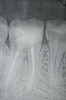

Ilyas1701 Опубликовано 20 августа, 2013 Автор Поделиться Опубликовано 20 августа, 2013 (изменено) Снимок вылеченной 46 (если я правильно понял обозначения зубов в стоматологии, а так он снизу справа 6 от центра) спустя 5 дней после леченияЕще сегодня вечером поднялась температура немного....правда я и без зубов болел не так давно, тоже была температура+ инфа: спустя 5 дней он реагирует еще на надкусывание, боль не дикая, в виски и в ухо сильнее вроде как не отдает, но тем не менее она есть Изменено 20 августа, 2013 пользователем Ilyas1701 Ссылка на комментарий

juli63 Опубликовано 20 августа, 2013 Поделиться Опубликовано 20 августа, 2013 Здравствуйте. В 46 зубе конкретный периодонтит, который начал обостряться. Единственное решенее- идти в другую клинику.Я не могу понять, чем руководствуется пациент, когда добровольно собирается наступить на те же грабли? Вас вводят в заблуждение. Какие гарантии, о чем речь? Рискуете заработать осложнение заболевания. По возможности ищите эндодонтиста. Ссылка на комментарий

Alisa st Опубликовано 21 августа, 2013 Поделиться Опубликовано 21 августа, 2013 Между корнями трещина, или мне кажется? Ссылка на комментарий

red_butler Опубликовано 21 августа, 2013 Поделиться Опубликовано 21 августа, 2013 Между корнями трещина, или мне кажется?Скорее всего это артефакт, связанный с тем, что снимок распечатан не на фотобумаге Ссылка на комментарий